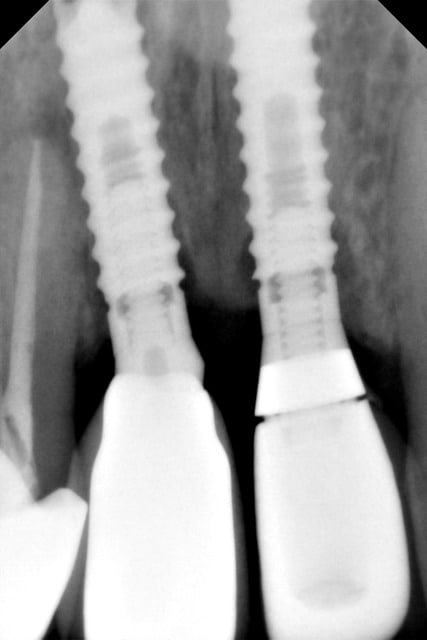

TBR col zircone z1

connexion oct in